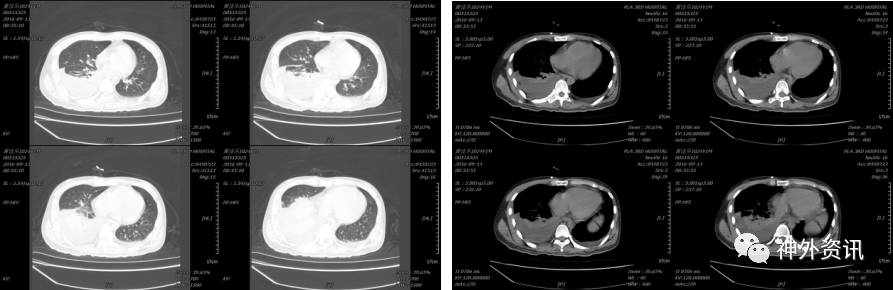

2015-12-02 12:33 伤后1小时我院急诊科复查头颅CT(2015-12-02 12:33):

入科后急诊在全麻下行去骨瓣减压及硬膜下血肿清除术,植入脑实质内颅内压监测,术后患者颅内压正常范围,生命体征平稳,术后第二日复查头颅CT及胸部CT(术后约14小时,2015-12-03 09:33):

患者术后虽然颅内显示正常,但挫伤出血量大,脑肿胀明显,行二次开颅颅内血肿清除术,术后复查头颅示(2015-12-04 09:05):

术后给予镇痛、镇静、机械通气、脱水、止血、抗感染、目标性体温控制、营养支持等治疗,术后4天复查头颅CT及胸部CT示(2016-12-08 10:39):